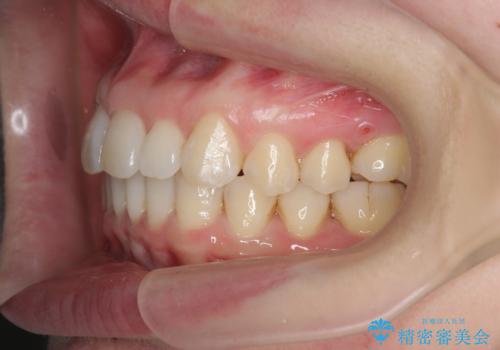

インビザライン で治す 出っ歯の治療

- 前歯の突出感、出っ歯の治療を希望され来院されました。

インビザラインを用いた治療計画を立て、しっかりと出っ歯を治すためにマイクロインプラントを併用します。

マイクロインプラントを併用することでしっかりとマウスピース全体を後方へ引き、前歯の突出感を改善することができました。